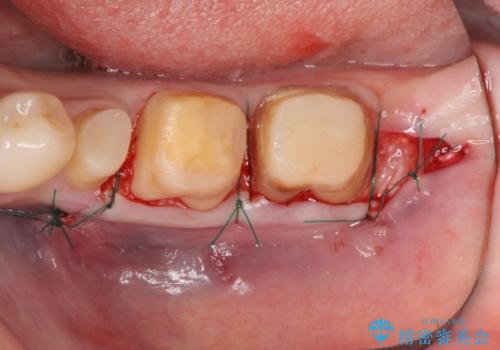

虫歯を除去すると、歯ぐきよりも深い虫歯であることが判明したため歯周外科を行い問題を解決していきます。

歯ぐきの炎症は虫歯や歯周病の再発原因となるため歯周外科による解決が望ましいです。

- 外科手術のため、術後に出血、痛みや腫れ、違和感を伴います